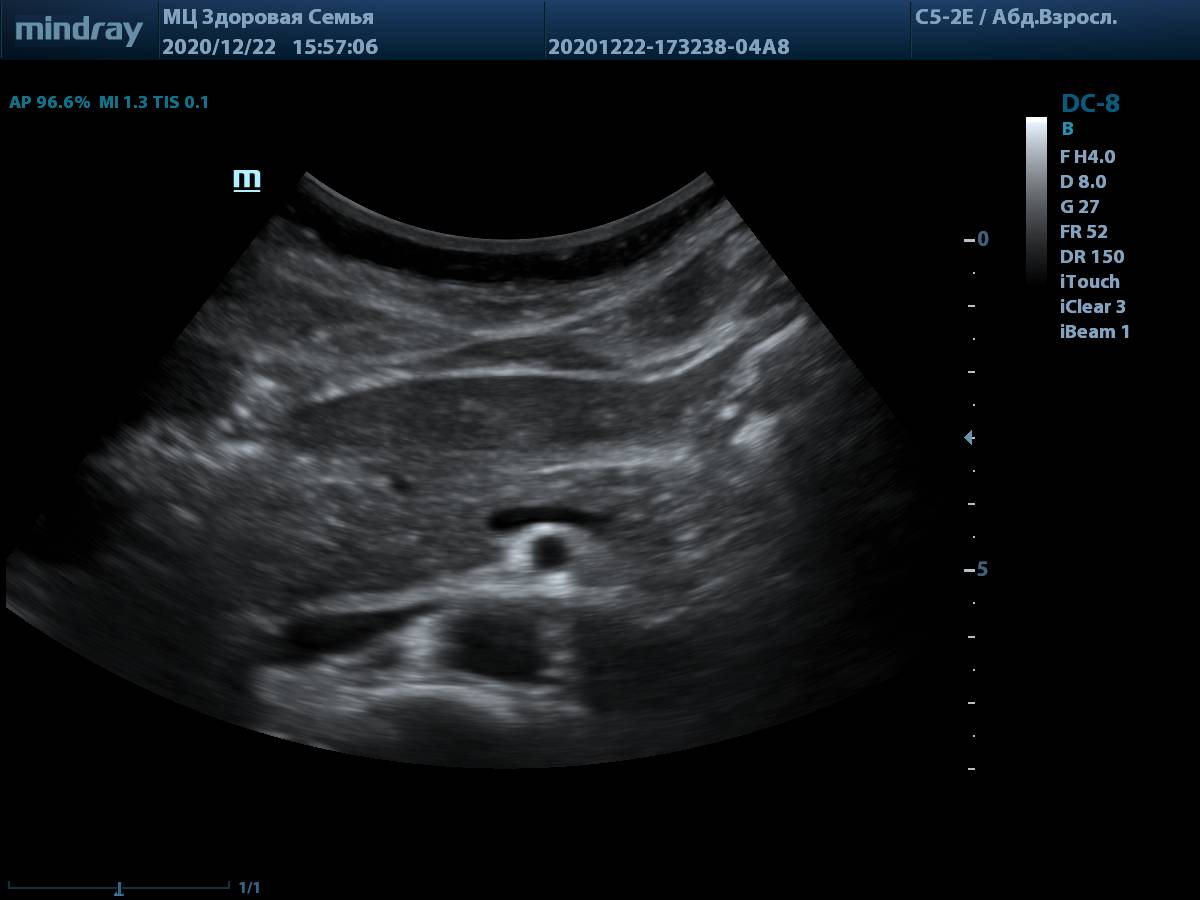

4. Пример визуализации поджелудочной железы у пациента с избытком массы тела, проблем с измерением органа и оценки его структуры нет. В качестве линзы использована левая доля печени.

Визуализации поджелудочной железы